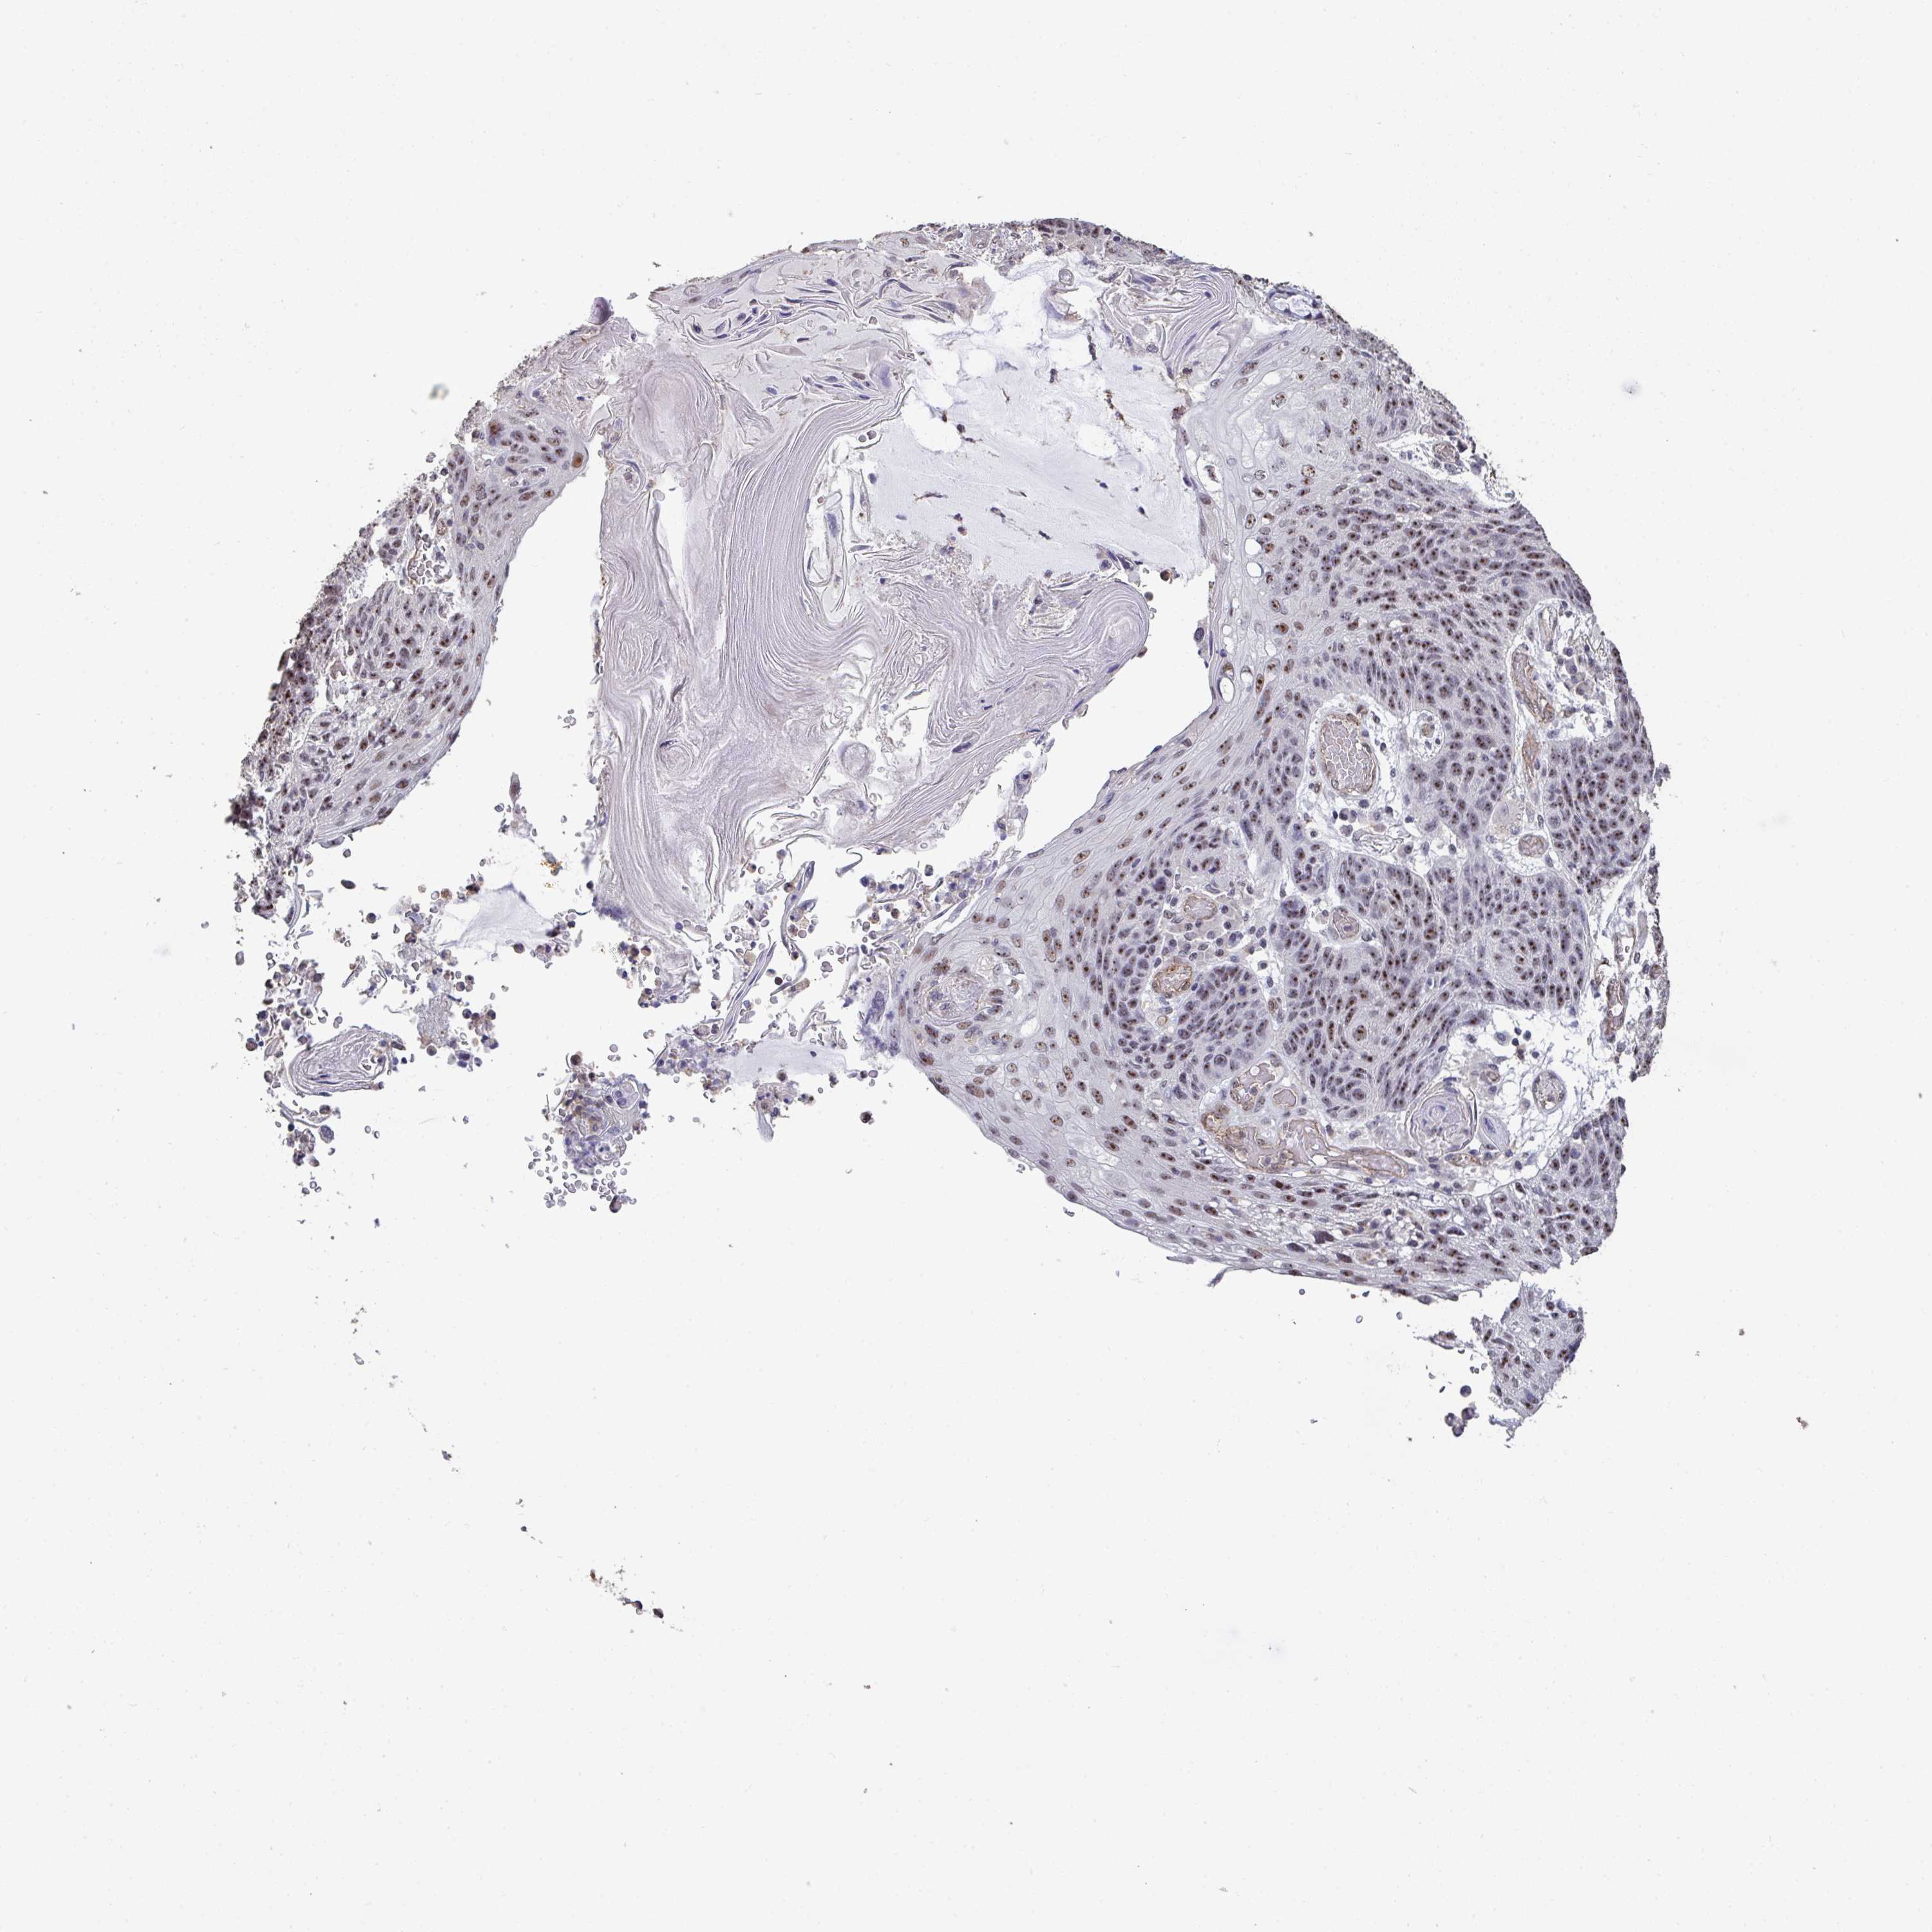

LUNG SQUAMOUS CELL CARCINOMA (TCGA) - Interactive survival scatter ploti

The Survival Scatter plot shows the clinical status (i.e. dead or alive) for all individuals in the patient cohort, based on the same data that underlies the corresponding Kaplan-Meier plots. Patients that are alive at last time for follow-up are shown in blue and patients who have died during the study are shown in red.

The x-axis shows the expression levels (FPKM) of the investigated gene in the tumor tissue at the time of diagnosis. The y-axis shows the follow-up time after diagnosis (years). Both axes are complimented with kernel density curves demonstrating the data density over the axes. The top density plot shows the expression levels (FPKM) distribution among dead (red) and alive patients (blue). The right density plot shows the data density of the survived years of dead patients with high and low expression levels respectively, stratified using the cutoff indicated by the vertical dashed line through the Survival Scatter plot. This cutoff is automatically defined based on the FPKM cutoff that minimizes the p-score. The cutoff can be changed by dragging the vertical line or by entering a cutoff value in the square labeled "Current cut-off".

Under the Survival Scatter plot the p-score landscape (black curve; left axis) is shown together with dead median separation (red curve; right axis). Dead median separation is the difference in median mRNA expression between patients who have died with high and low expression, respectively. It is calculated as follows: median FPKM expression of dead patients with high expression - median FPKM expression of dead patients with low expression. This is intended to aid the user in visually exploring custom cutoffs and the associated p-scores and dead median separation.

Individual patient data is displayed and can be filtered by clicking on one or more of the category buttons on the top of the page. Categories describing expression level and patient information include: high, low, alive, dead, female, male and tumor stages. The scale of the x-axis can be toggled between linear and log-scale by clicking on the "x log" button. Mouse-over function shows TCGA ID, patient information and mRNA expression (FPKM) for each patient.

& Survival analysisi

Kaplan-Meier plots summarize results from analysis of correlation between mRNA expression level and patient survival. Patients were divided based on level of expression into one of the two groups "low" (under cut off) or "high" (over cut off). X-axis shows time for survival (years) and y-axis shows the probability of survival, where 1.0 corresponds to 100 percent.

SENP3 is not prognostic in Lung Squamous Cell Carcinoma (TCGA)

Best expression cut offi

Based on the FPKM value of each gene, patients were classified into two groups and association between prognosis (survival) and gene expression (FPKM) was examined. The best expression cut-off refers the FPKM value that yields maximal difference with regard to survival between the two groups at the lowest log-rank P-value. Best expression cut-off was selected based on survival analysis .

When clicking on this number, the vertical dashed line indicating cut-off, the interactive survival plot, and the Kaplan-Meier curve will be adjusted to show results based on the best expression cut-off.

: 29.4